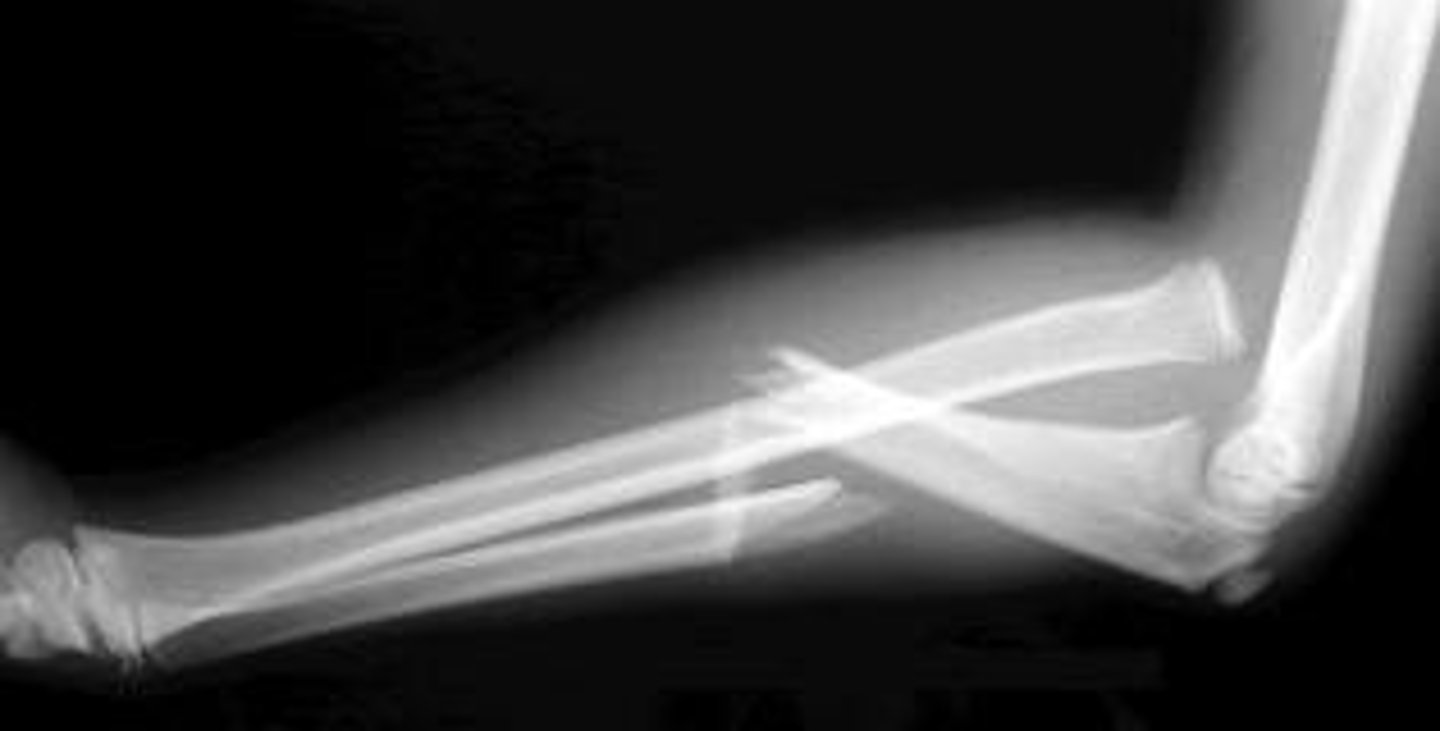

What is a Monteggia fracture?

- dislocation of proximal radioulnar joint

- ulnar fracture

What is the most common type of Monteggia fracture?

Bado Type I

- fracture of the proximal 1/3 ulna

- anterior dislocation of radius

What is a Galeazzi fracture?

fracture of radial shaft

- oblique/transverse Fx

dislocation of the distal radioulnar joint

What is the treatment for Monteggia and Galeazzi fractures in adults vs. children?

Adults → ORIF

- non-surgical Tx has increased risk for displacement

Children → closed reduction and casting